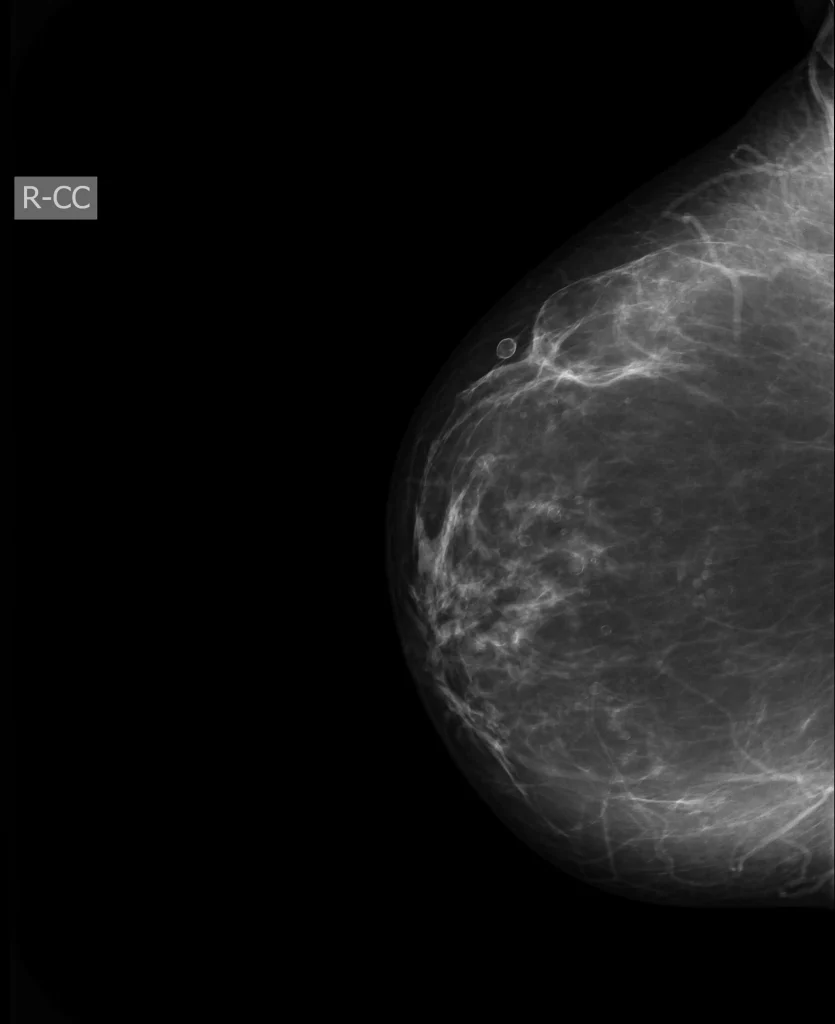

در مواردی که نیاز به تعیین دقیق نوع باکتری باشد، پزشک از چرک نمونهبرداری کرده و برای کشت میفرستد تا آنتیبیوتیک مناسب انتخاب شود. - MRI یا ماموگرافی

در موارد پیچیده یا مشکوک به بیماری زمینهای مانند تومور، MRI یا ماموگرافی انجام میشود.